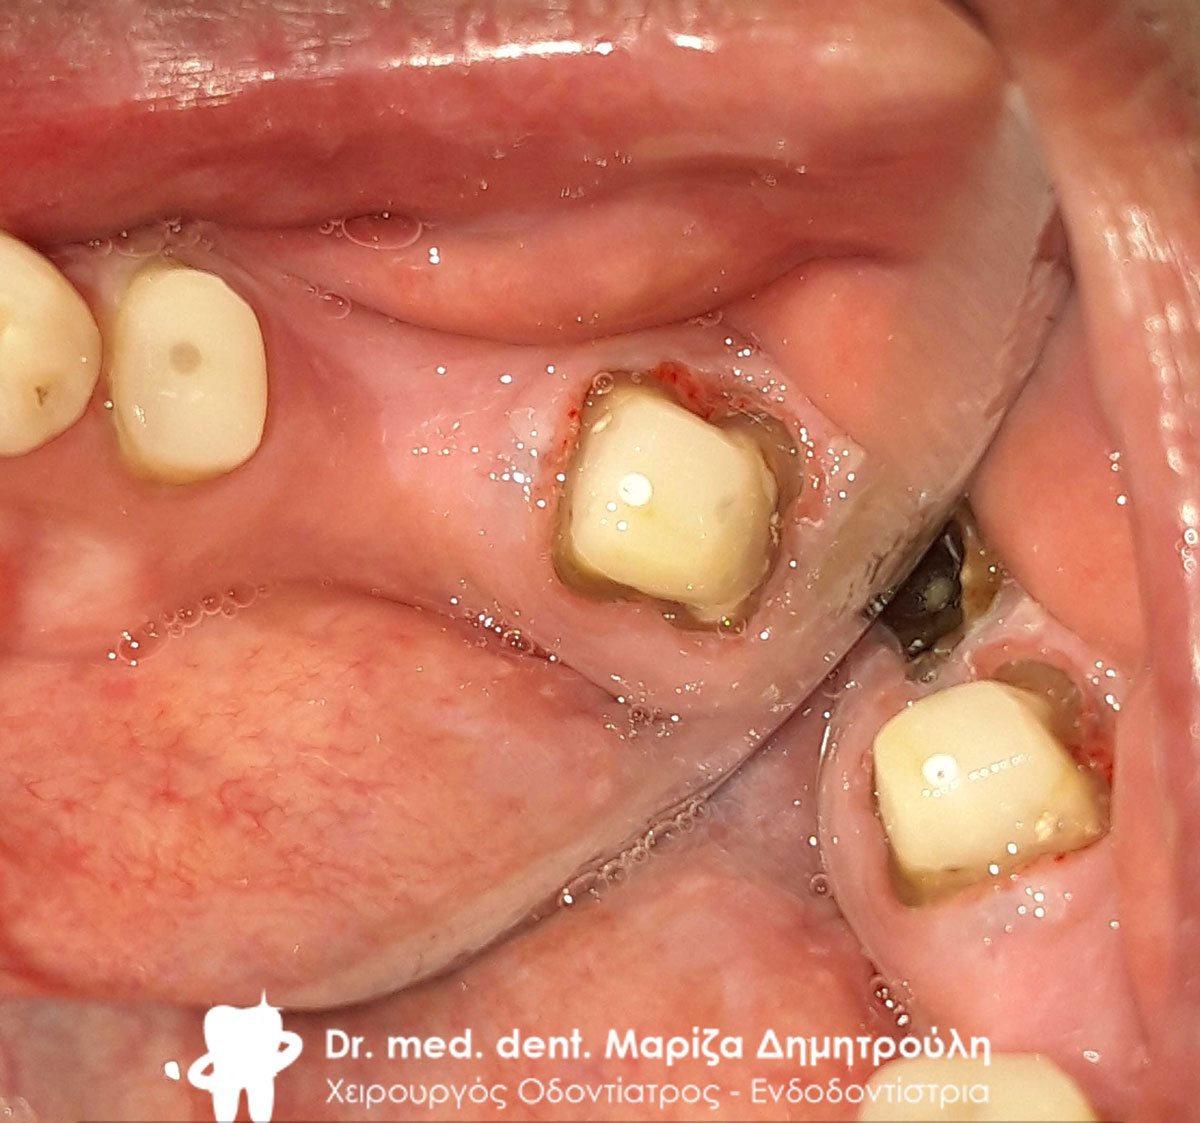

Εικόνα του δεύτερου προγόμφιου μετά την ολοκλήρωση της απονεύρωσης και πριν την ανασύσταση του δοντιού με άξονα

Εικόνα του δεύτερου προγόμφιου μετά την ολοκλήρωση της απονεύρωσης και πριν την ανασύσταση του δοντιού με άξονα

Αργότερα εκδήλωσε έντονο πόνο στο δεύτερο προγόμφιο της αριστερής πλευράς της άνω γνάθου. Πραγματοποιήθηκε απονεύρωση και το δόντι ανασυστάθηκε με λευκό άξονα υαλονημάτων και λευκή ρητίνη. Σε δεύτερη φάση θα κατασκευαστεί ολοκεραμική θήκη ζιρκονίου που θα καλύψει το δόντι.